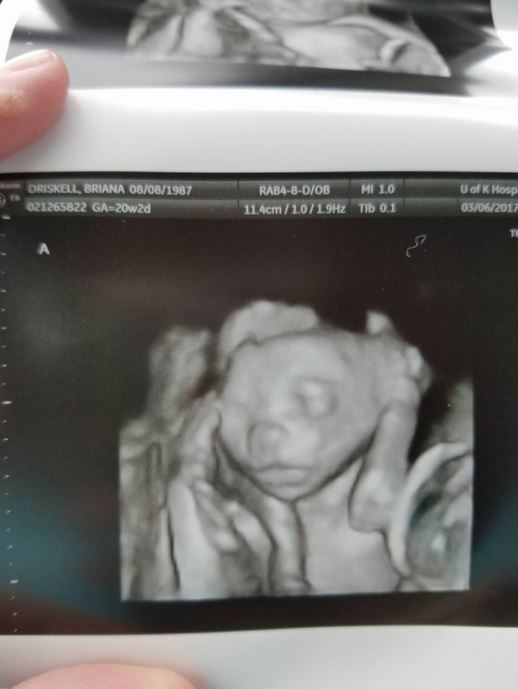

透過超音波畫面可以看到,布萊安娜肚子裡竟然出現五個胎兒!之前一直不懷孕,沒想到一來就是五個,戲劇性的變化讓她相當震撼,「我是真的差點暈倒!」

「我當時震驚到說不出話,就做在那裡呆瞪著螢幕,完全不敢相信。我真的不知道我可以一次懷上五個寶寶。」雖然曾出現過不少多胞胎的案例,但實際上來說,懷上三胞胎的機率低於5%,而像布萊安娜這樣的五胞胎,機率更是只有5千萬分之一!